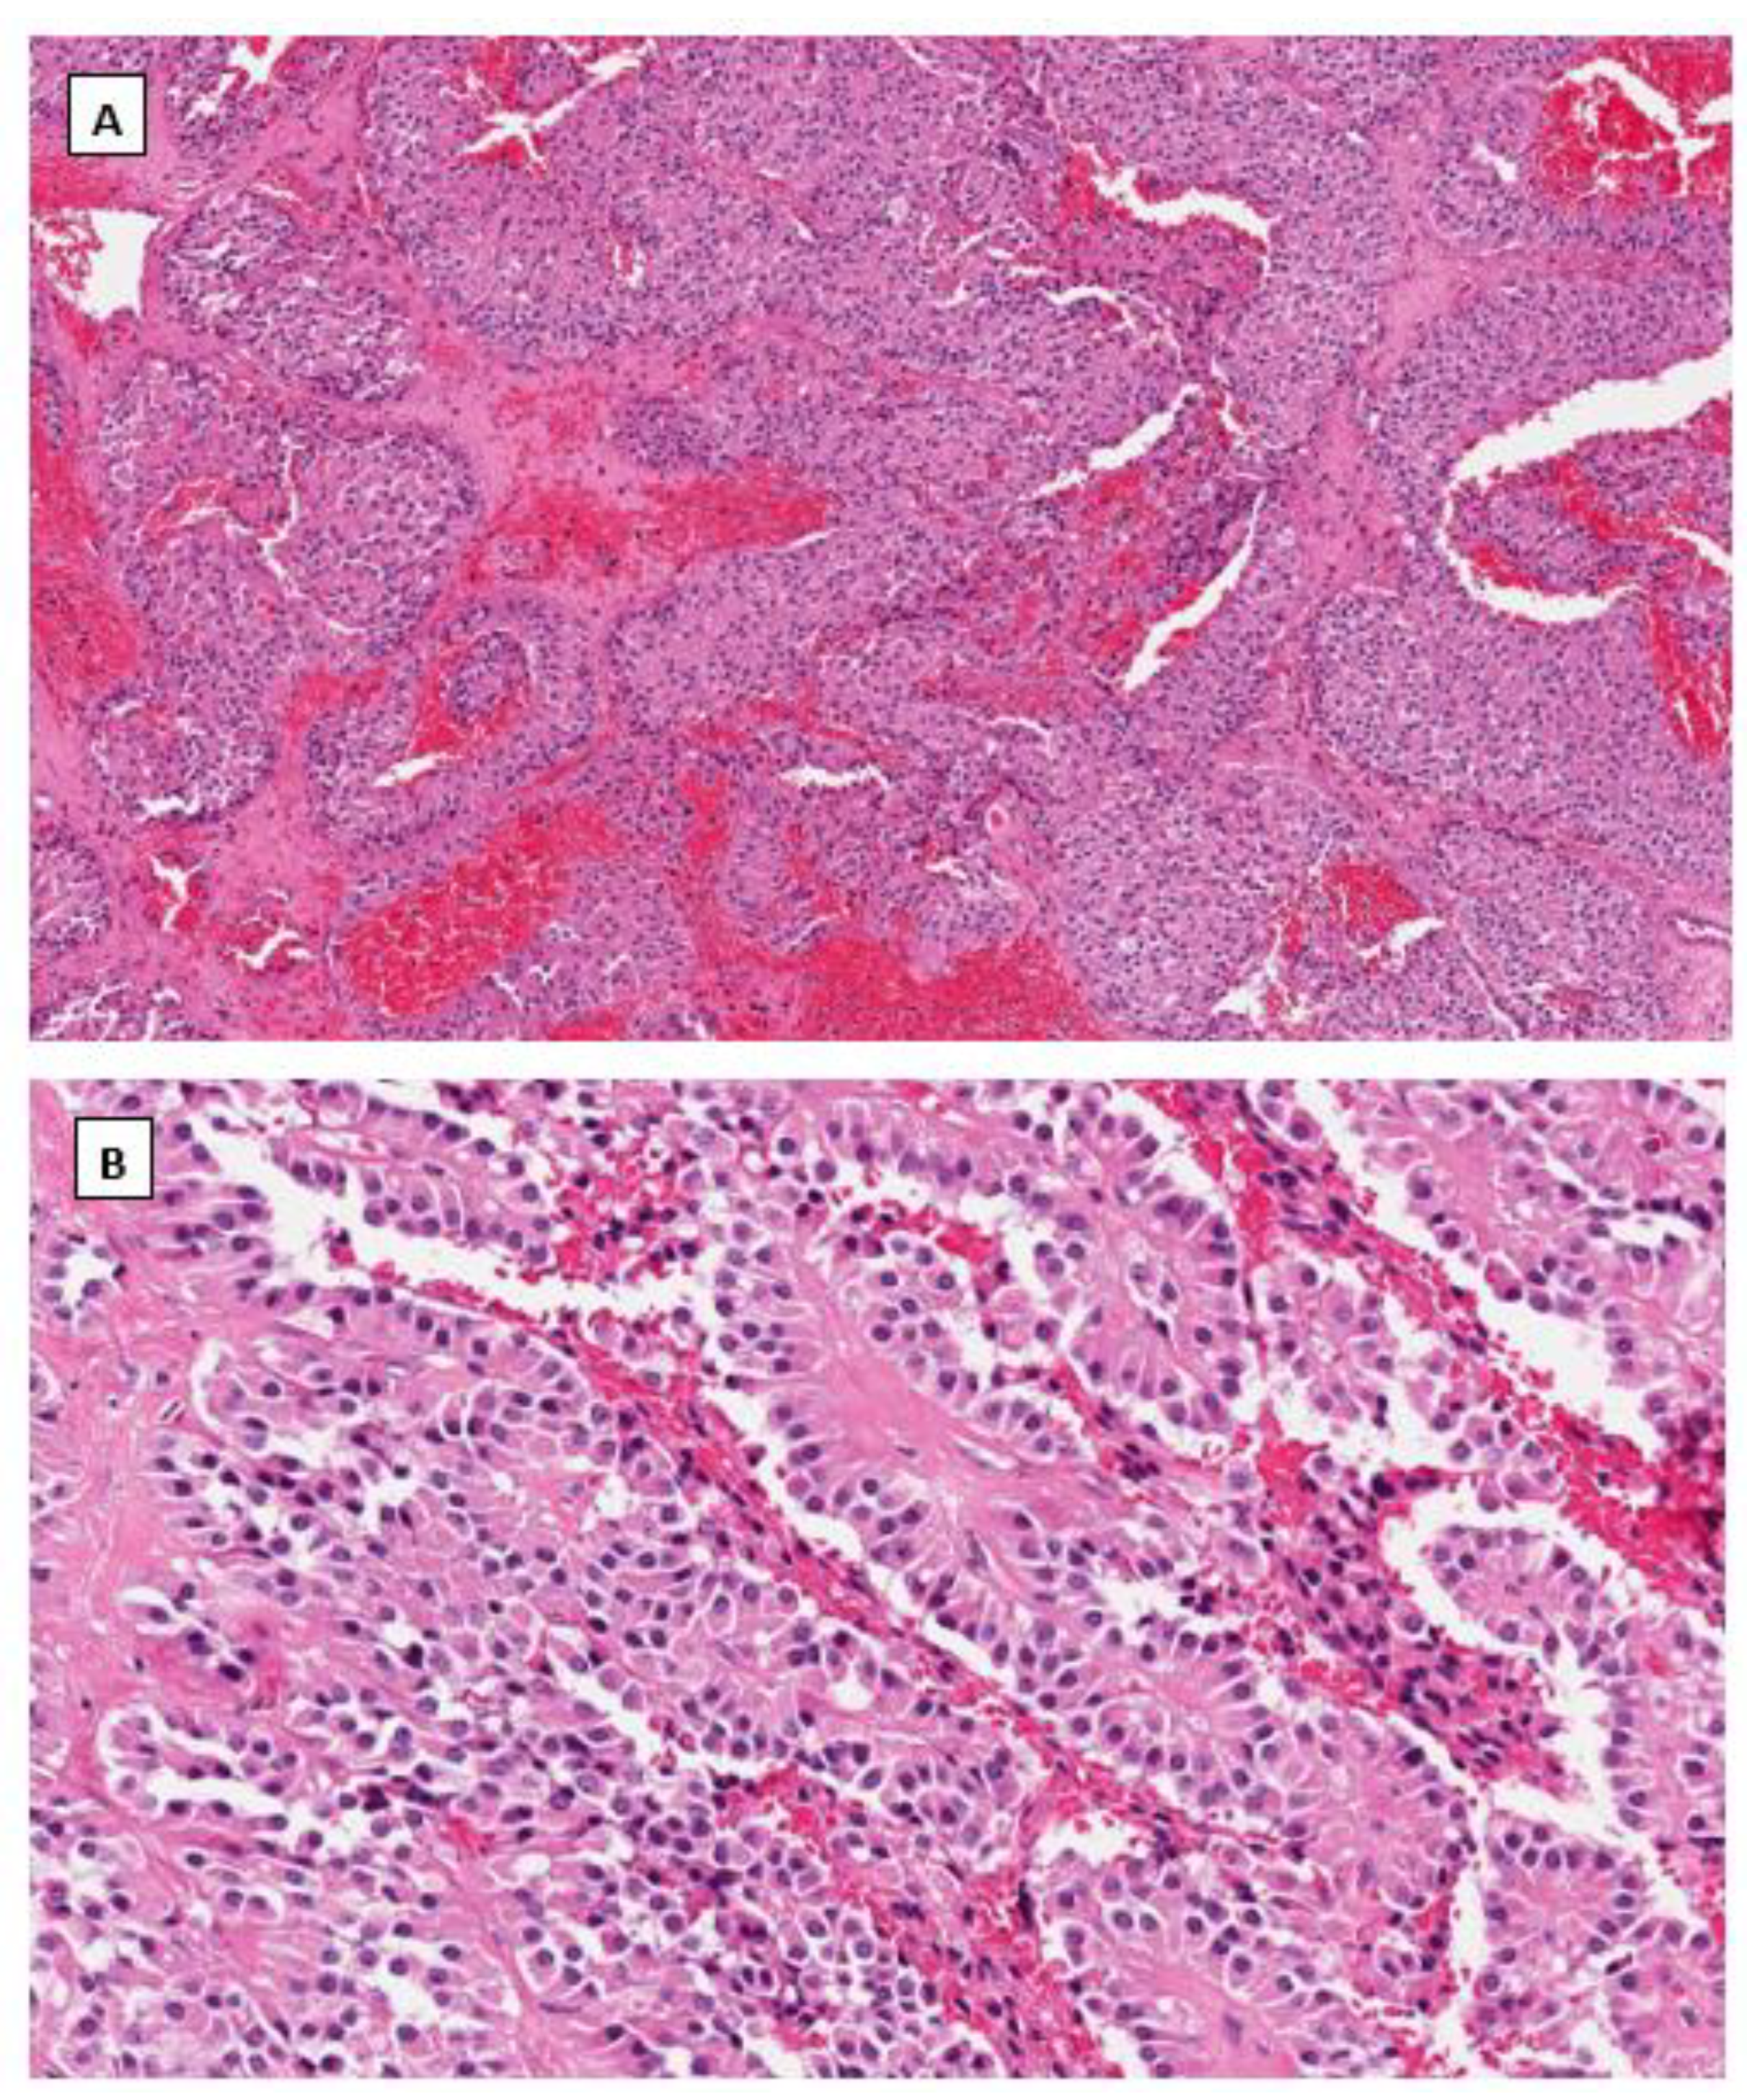

4.1. Solid Pseudopapillary Neoplasm (SPPN)

4.2. Microcystic Stromal Tumor (MCST)